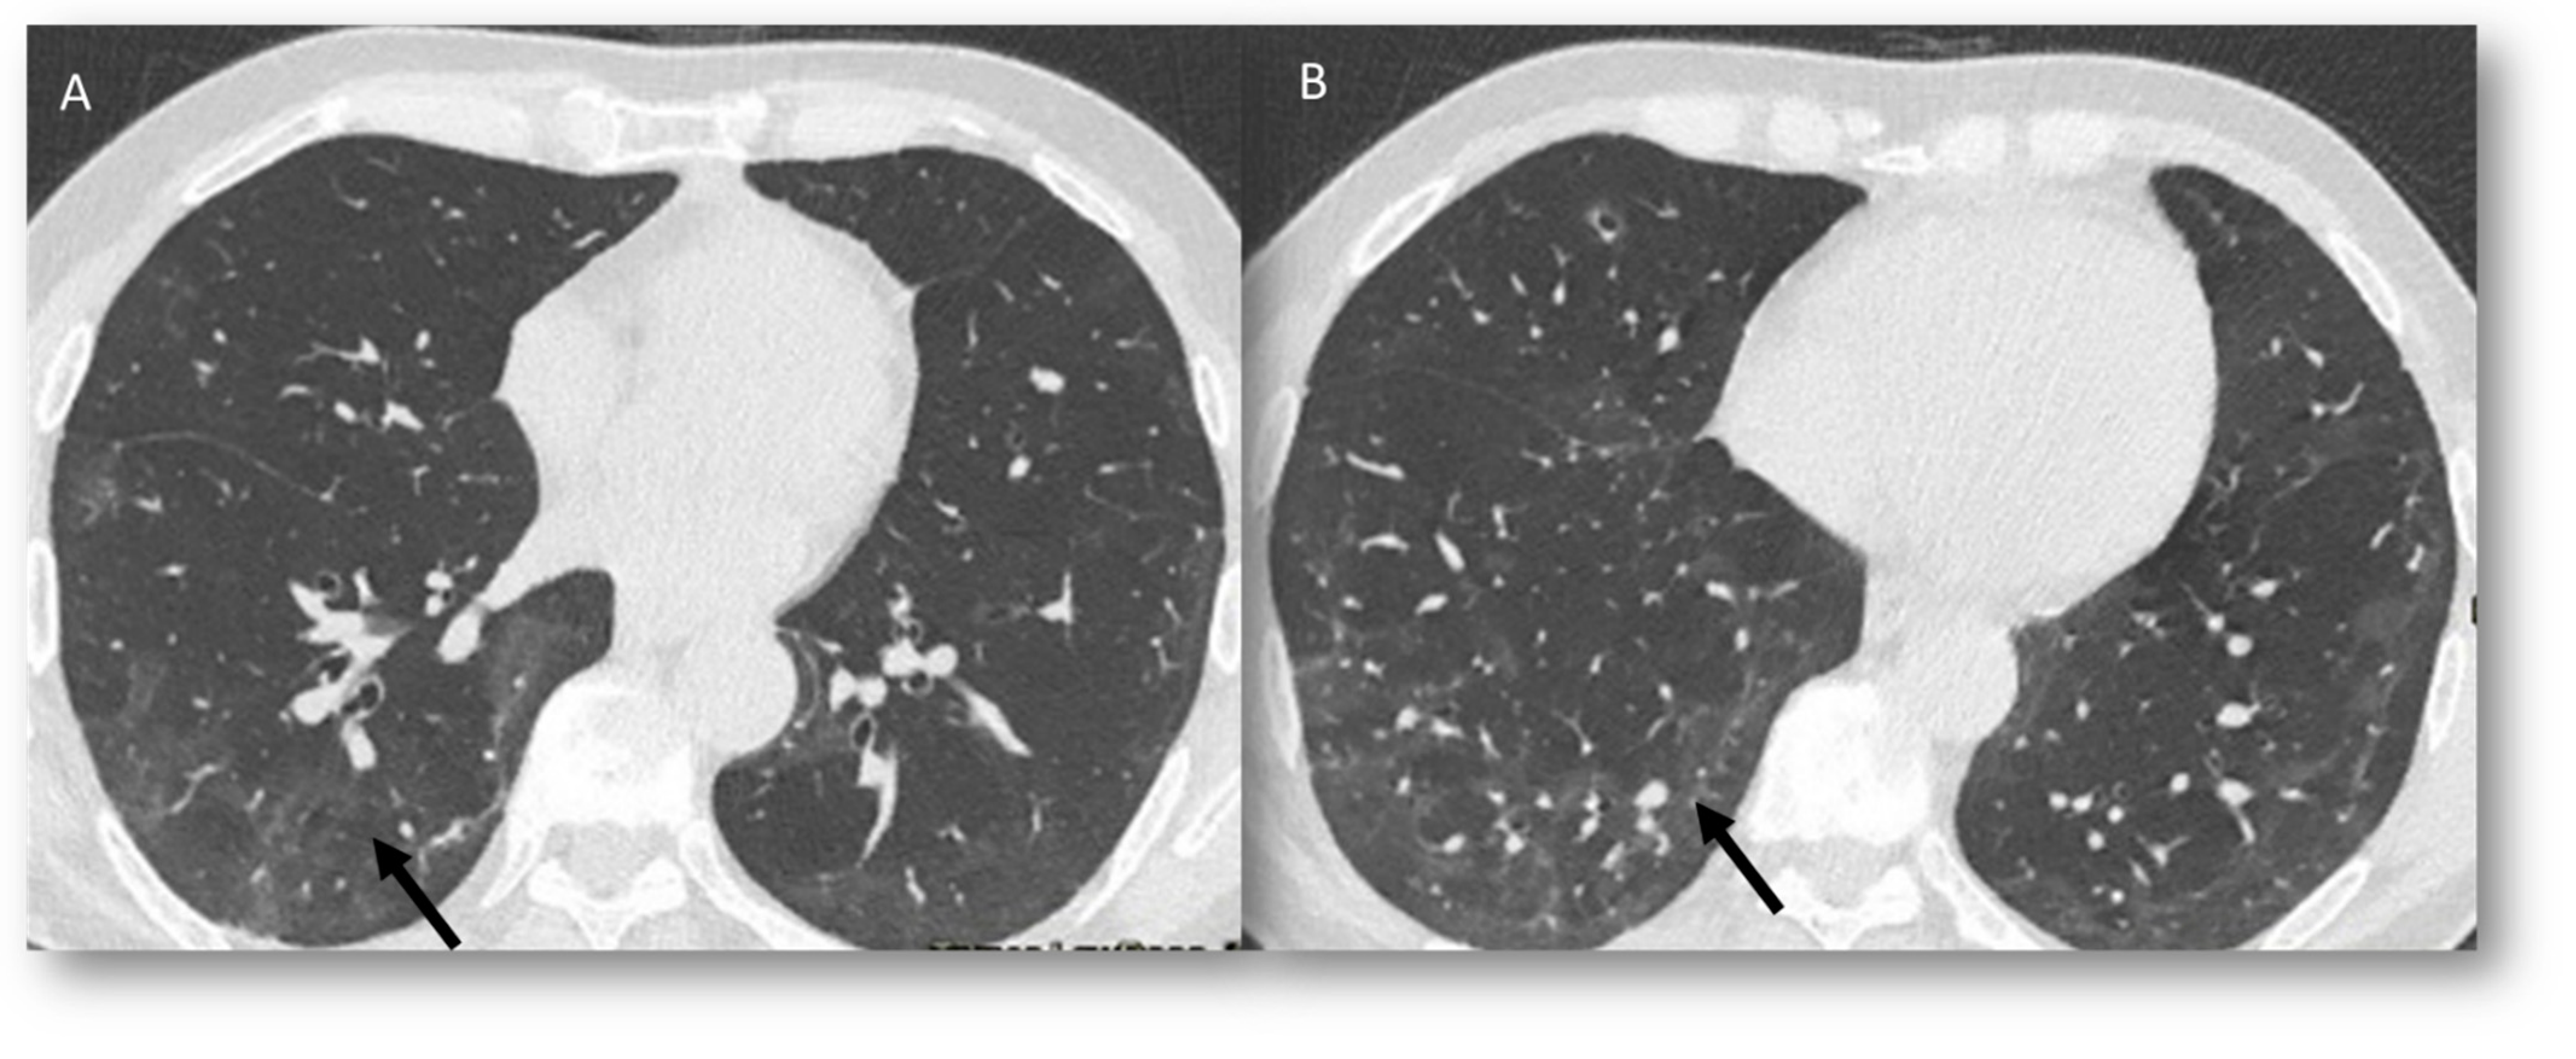

Radiation Recall Pneumonia

| RRP | Target area | Ground-glass opacities and consolidative opacities. | Unknown (A non-immune fixed drug reaction-like condition, dysregulated release of reactive oxygen species, abnormalities of tissue vasculature and impaired DNA repair). |

| RP | Target area | Ground-glass opacities and consolidative opacities. | Direct damage to the DNA and indirect damage through the production of reactive oxygen species (ROS), causing changes in vascularity and capillary permeability, activation of the inflammatory response and alteration of immunological response |